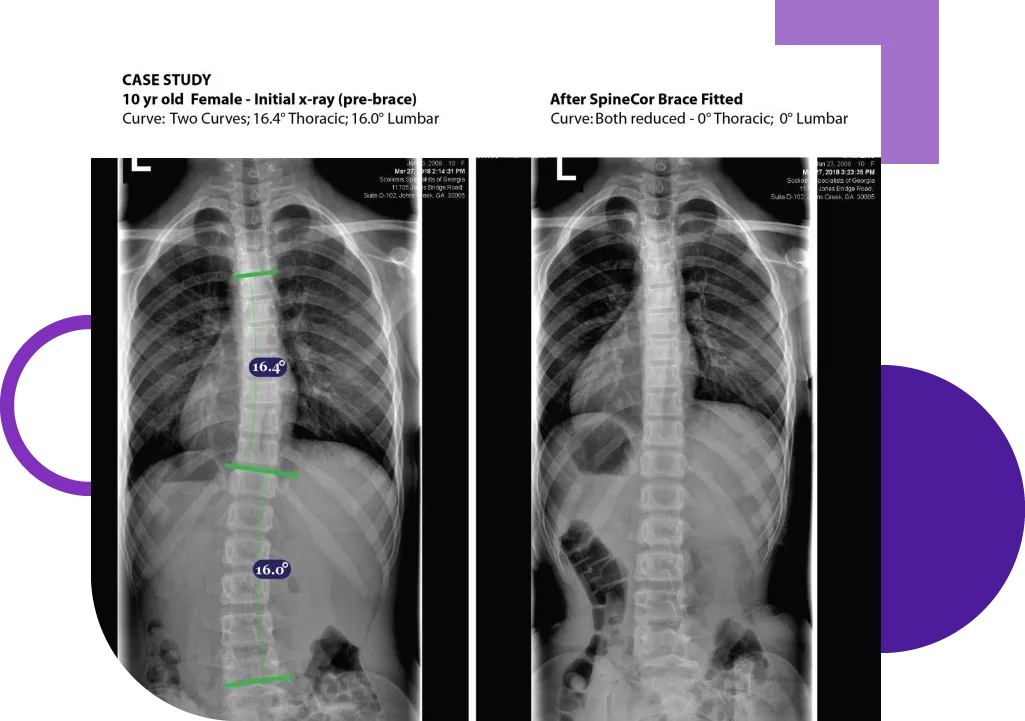

Before & After Treatment

Same Day Results

The two X-rays on the left were taken MINUTES apart from each other, not years. In most cases a significant reduction in Scoliosis takes place INSTANTLY once our SpineCor Dynamic soft brace is custom fit to the patient.